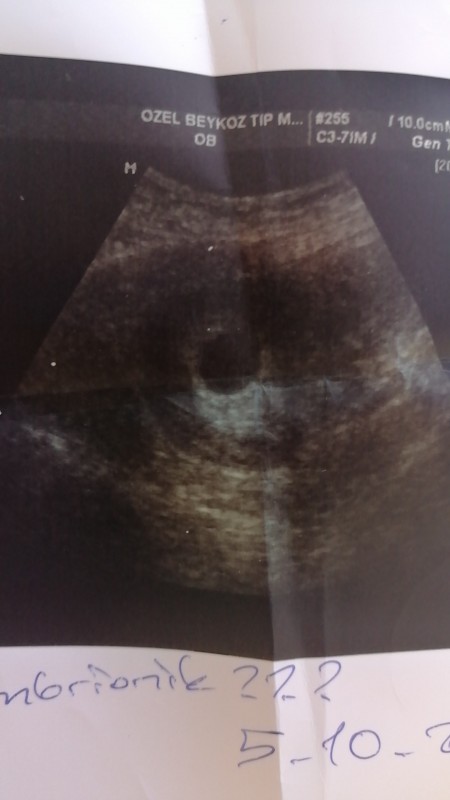

Kese Var Bebek Yok

Kese Var Bebek Yok.

6 0 da kese var bebek yok boyle olup sonradan bebegin kalp atisini duyan var mi hamilelik donemi genel